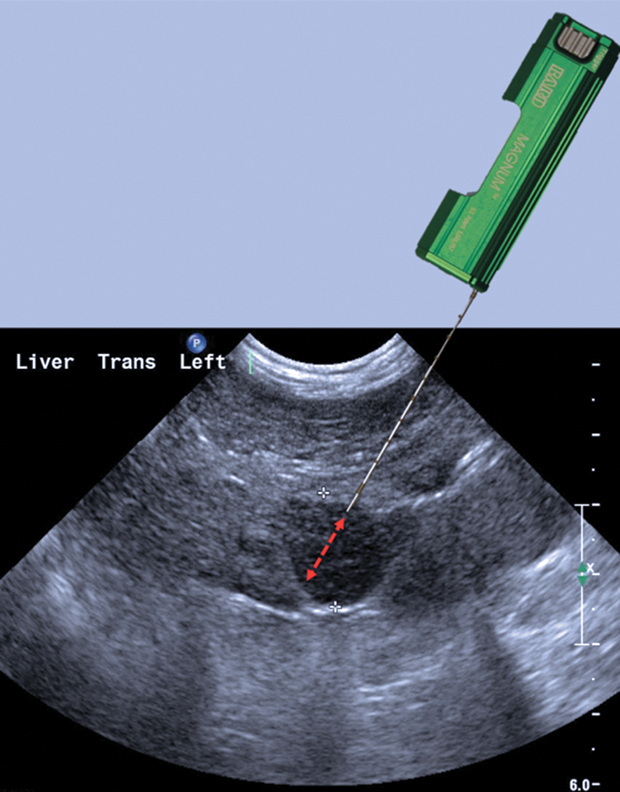

USG guided procedures – (hands-on biopsy / drainage on phantoms)

Coordinators:

Dr Franklin El. Irwin

Dr Jagadeesh Kumar Chitakala

Dr Joseph Chacko Paul